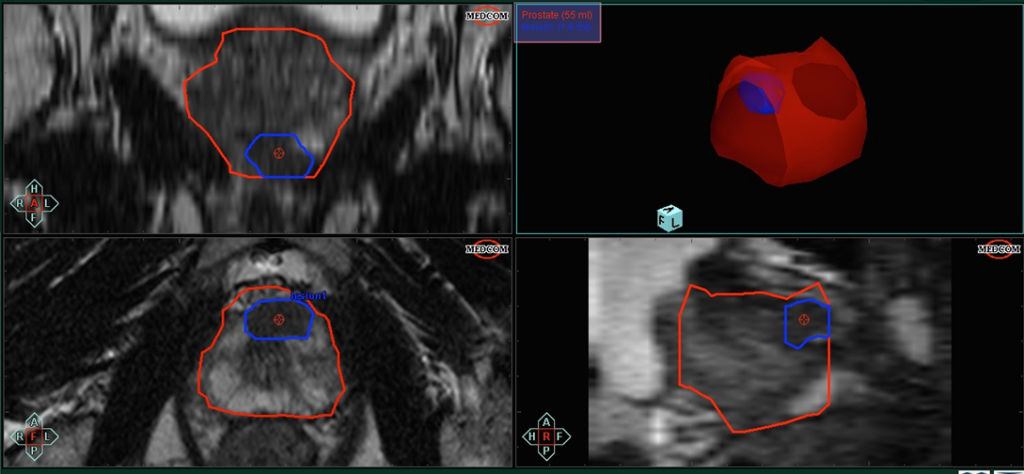

Που βοηθάει η διαπερινεϊκή πρόσβαση; (Βλ. Εικόνα 2)

Το περίνεο ανατομικά είναι η περιοχή μεταξύ όρχεων και πρωκτού. Στην διαπερινεϊκή βιοψία προστάτη το υπέρηχο που απεικονίζεται ο προστάτης μπαίνει στο ορθό, αλλά οι λήψεις των δειγμάτων βιοψιών γίνεται από την περιοχή του περινέου και το έντερο αποφεύγεται εντελώς.

- Πρόσβαση σε δύσκολα ανατομικά περιοχές: Με την περινεϊκή πρόσβαση βλάβες στην πρόσθια ζώνη, στην μεταβατική ζώνη καθώς και στον μέσο λοβό είναι εύκολα προσβάσιμες σε αντίθεση με την διορθική που οι περιοχές αυτές βρίσκονται μακριά από το έντερο. Με τον τρόπο αυτό με την διαπερινεϊκή πρόσβαση όπου και να βρίσκονται οι βλάβες είναι δυνατόν να παρακεντηθούν.

Εικόνα 2: Η πρόσβαση από το περίνεο αποφεύγει το έντερο και είναι εφικτό να στοχεύσει ακόμα και βλάβες απομακρυσμένες όπως στην πρόσθια ζώνη και στον μέσο λοβό Συνολικά, η διαπερινεϊκή πρόσβαση είναι μια χρήσιμη επιλογή στη βιοψία προστάτη και προσφέρει πλεονεκτήματα όσον αφορά την ασφάλεια και την ακρίβεια. Η πρόσβαση από το περίνεο αποφεύγει το έντερο και είναι εφικτό να στοχεύσει ακόμα και βλάβες απομακρυσμένες όπως στην πρόσθια ζώνη και στον μέσο λοβό. Συνολικά, η διαπερινεϊκή πρόσβαση είναι μια χρήσιμη επιλογή στη βιοψία προστάτη και προσφέρει πλεονεκτήματα όσον αφορά την ασφάλεια και την ακρίβεια.

Αν έχω μικρή βλάβη στην πρόσθια ζώνη ή στον μέσο λοβό μπορώ με την διαπερινεϊκή βιοψία να εξασφαλίσω την λήψη; (Βλ. Εικόνα 3)

Η διαπερινεϊκή πρόσβαση είναι εντελώς διαφορετική από την διορθική και ακόμα και βλάβες σε δύσκολα ανατομικά περιοχές όπως στην πρόσθια ζώνη και στον μέσο λοβό είναι εύκολα προσβάσιμες από το περίνεο.Το περίνεο είναι η ιδανική προσέγγιση καθώς ολόκληρος ο προστάτης είναι σε επαφή με το περίνεο και ο ουρολόγος με βάση τις εικόνες της μαγνητικής μπορεί να κατευθύνει την βελόνα όπου υπάρχει βλάβη.Η πρόσθια ζώνη και ο μέσος λοβός δεν αποτελούν εξαίρεση καθώς με την απλή μετακίνηση της βελόνας προς την επιθυμητή περιοχή λαμβάνεται άνετα δείγμα από τις περιοχές αυτές.Για το λόγο αυτό η διαπερινεϊκή fusion βιοψία προστάτη θεωρείται ότι έχει την μεγαλύτερη διαγνωστική ακρίβεια.

Αν έχω μικρή βλάβη στην πρόσθια ζώνη ή στον μέσο λοβό μπορώ με την διορθική βιοψία να εξασφαλίσω την λήψη; (Βλ. Εικόνα 2)

Εικόνα 2: Βλάβη σε μέσο λοβό που όπως απεικονίζεται βρίσκεται απομακρυσμένα από το έντερο με αποτέλεσμα να είναι δύσκολή η διορθική προσέγγιση των ύποπτων αυτών περιοχών καθιστώντας την τεχνική αυτή λιγότερο αξιόπιστη για την δειγματοληψία βλαβών σε μέσο λοβό και πρόσθια ζώνη